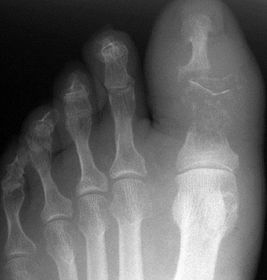

| Describe the alignment of metatarsal 2 | There is no angulation nor displacement of the distal segment relative to the proximal segment. |

| Describe the alignment of metatarsal 3 | The distal segment is displaced laterally (50% apposition) and angulated medially. |

| Describe the alignment of metatarsal 4 | The distal segment is displaced laterally (75% apposition) but there is no apparent angulation. |

| Describe the tubulation of the metatarsals | Metatarsals are overtubulated - decreased girth. |

| Describe the tubulation of the metatarsals | Metatarsals are undertubulated - increased girth. |